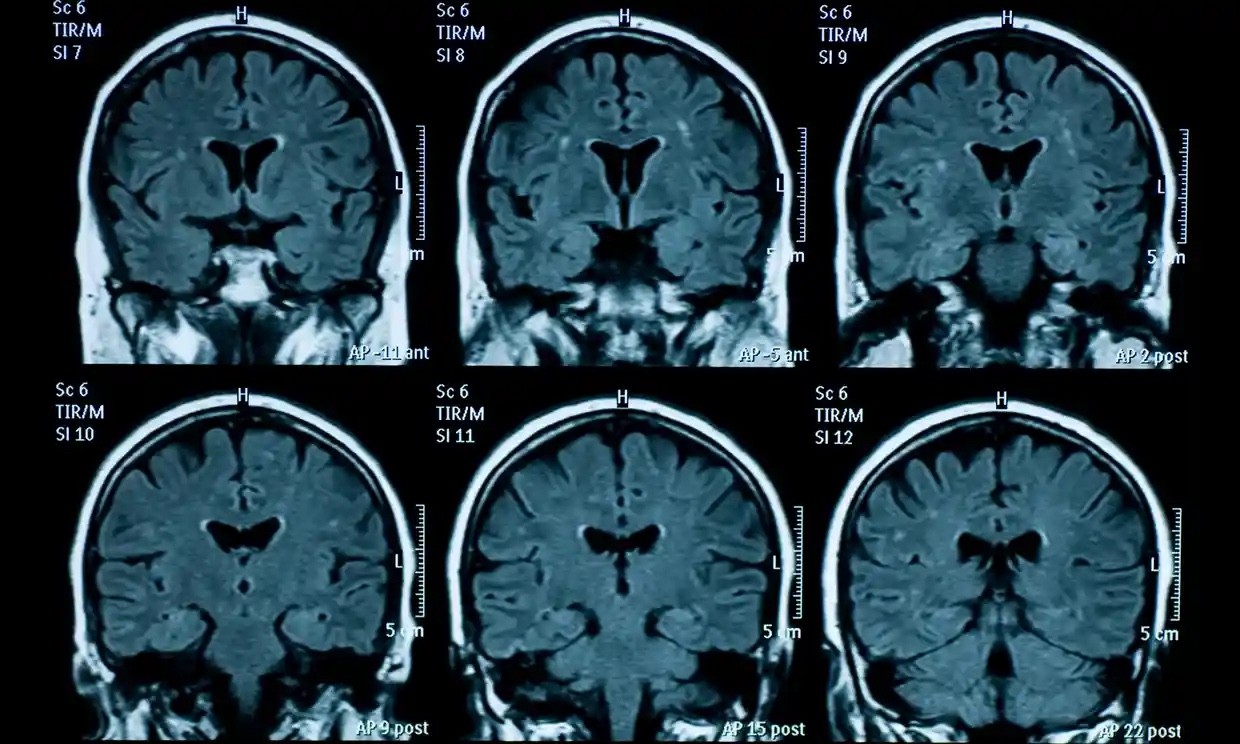

| Qua hình ảnh chụp MRI một người trải quan thời gian đại dịch Covid-19, các nhà nghiên cứu nhận thấy sự khác biệt về tuổi não là khoảng ba năm. (Nguồn: Getty Images) |

Để thực hiện nghiên cứu, các nhà khoa học đã so sánh hình ảnh chụp cộng hưởng từ (MRI) của 81 thanh thiếu niên sống tại Mỹ được chụp trước thời kỳ đại dịch bùng phát (từ tháng 11/2016-11//2019) với kết quả MRI của 82 thanh thiếu niên chụp trong giai đoạn từ tháng 10/2020-3/2022, khi đại dịch vẫn hoành hành nhưng sau khi các biện pháp phong tỏa đã được dỡ bỏ.

Sau khi chọn ra 64 người tham gia trong mỗi nhóm có nhiều đặc điểm tương đồng, trong đó có đặc điểm về giới tính và độ tuổi, các nhà nghiên cứu phát hiện một số khác biệt đáng chú ý. Theo đó, sự thay đổi về cấu trúc vật lý của não bộ trong quá trình dậy thì - như vỏ não mỏng đi, sự phát triển của đồi hải mã và chất xám - xảy ra ở nhóm được chụp MRI sau phong tỏa nhiều hơn so với nhóm được chụp MRI trước đại dịch.

Giáo sư chuyên ngành tâm lý học của đại học Standford, Ian Gotlib, tác giả chính của nghiên cứu, cho biết chênh lệch về mức độ lão hóa não bộ giữa 2 nhóm là khoảng 3 năm. Các nhà nghiên cứu bất ngờ về mức chênh lệch nhiều như vậy trong khi các biện pháp phong tỏa chỉ kéo dài chưa đến 1 năm.